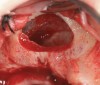

The technique described below is based on a deep buccal full-thickness flap with vertical release in the canine area, followed by creation of a “window” at the lateral wall of the sinus (Figure 2). The bony window is either removed or rotated medially with the sinus membrane and pushed inward. The Schneiderian membrane is then separated from the bone anteriorly, posteriorly, and medially until clinically sufficient space is established (Figure 3). The created space, which occupies the lower third of the sinus, is filled with a bone graft (Figure 4), and the lateral access window is covered with a collagen membrane (Figure 5).

Fig 3. Schneiderian membrane from the sinus walls is elevated.

Fig 4. Space is created between the Schneiderian membrane and the sinus walls filled with particulate xenograft.